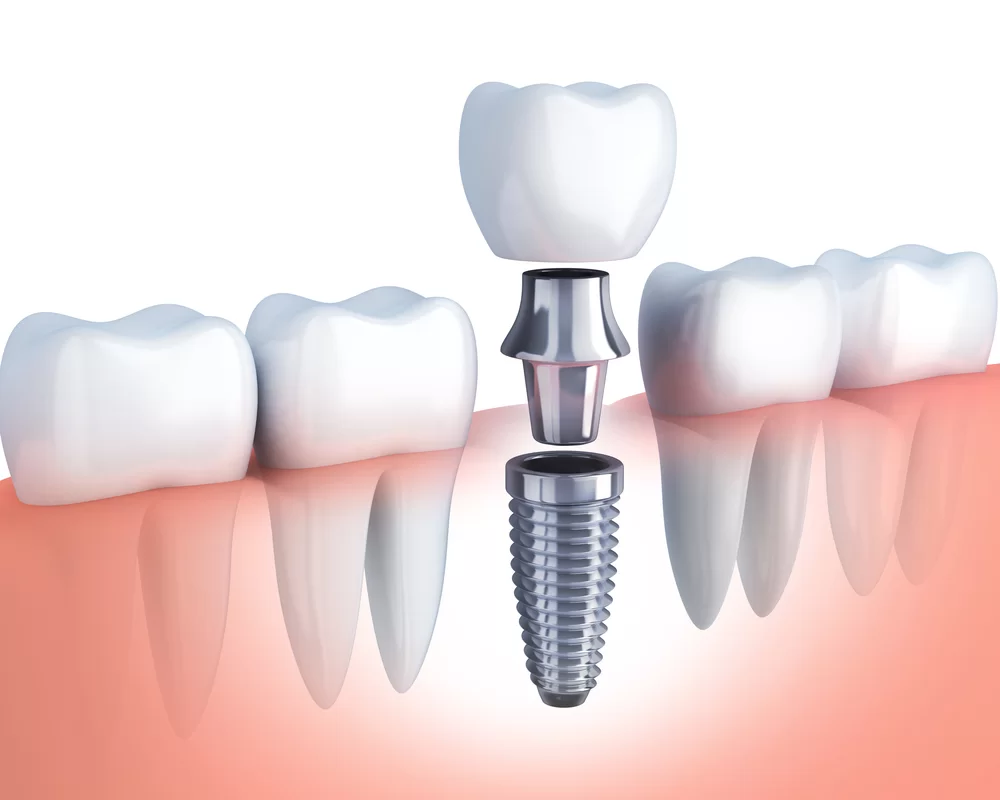

At Advanced Dental Care we believe in offering our patients what’s most appropriate from basically 3 alternative options for tooth replacement: Ideally an implant. Second choice would be “Crown and Bridge.” A less desirable, but a viable selection, would be a removable denture.

- Dental Implants